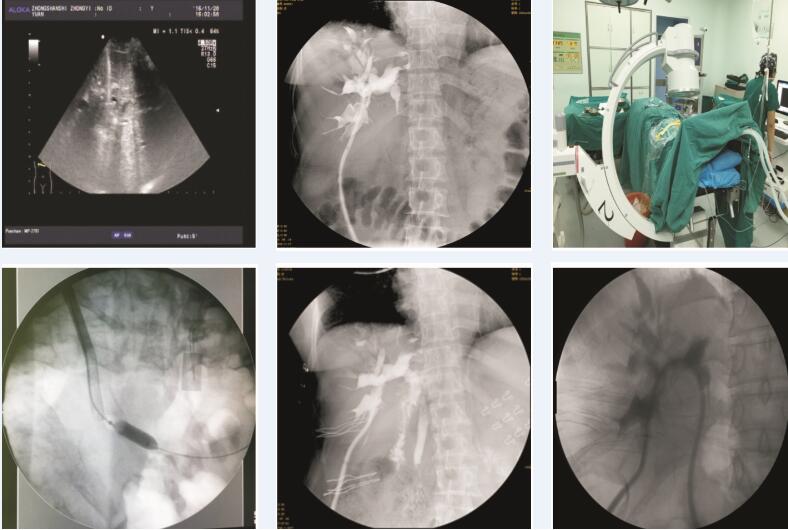

经皮胆道造瘘胆道镜取石、球囊扩张术治疗复发肝内胆管结石46例临床观察

陈壮浩, 李建明, 宋巍巍, 李伟, 郭锋满, 常建星

2020, 20(06):  699-702.  DOI: 10.3969/j.issn.1009-976X.2020.06.003

摘要 ( )   PDF (1826KB) ( )

参考文献 | 相关文章 | 计量指标

目的 探讨经皮胆道造瘘胆道镜取石、球囊扩张术治疗复发肝内胆管结石46例的临床价值。方法 回顾2015 年1月~2018年12月我院经皮胆道造瘘取石,球囊扩张术治疗复发肝内胆管结石患者46例的临床资料。结果 在46例复发肝内胆管结石患者中,完全取尽结石者43例(93.5%),术后胆道出血6例(13%),胆漏1例(2.2%),胆管炎4例(8.7%),发热8例,呕吐5例。无死亡病例,随访2年,6例(12.2%)结石复发。结论 经皮胆道造瘘胆道镜取石、球囊扩张术治疗复发肝内胆管结石取得良好的效果,取石安全有效,且微创,可作为胆道结石治疗手段的有效补充。